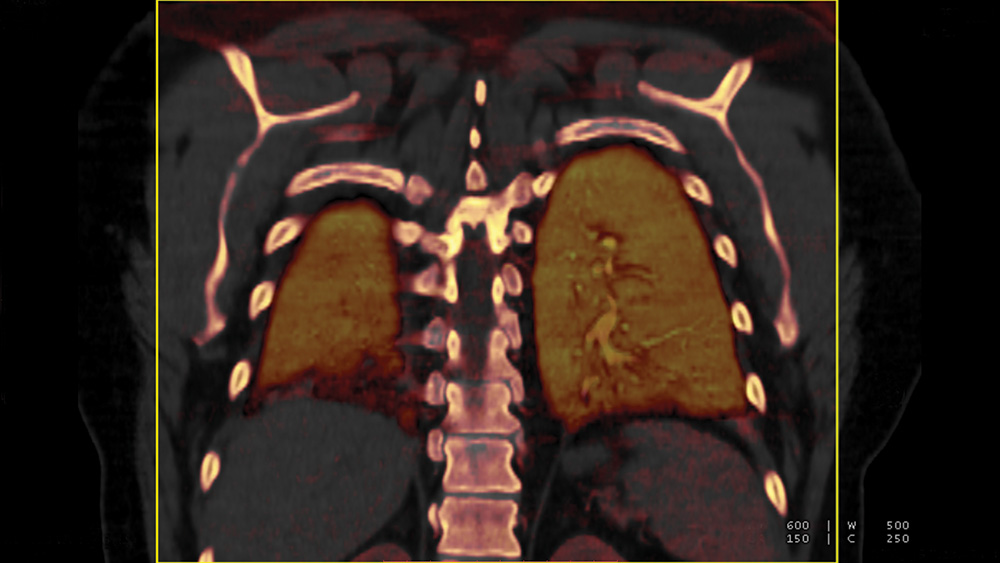

One of the most important recent advances in thoracic radiology and in vascular imaging in general has been the implementation of dual-energy CT.

Dual-energy CT allows the differentiation of materials with large atomic numbers such as iodine. Dual energy CT angiography can evaluate perfusion defects in cases of pulmonary embolism.

Although not as sensitive and specific as scintigraphy, it is highly accurate when there is complete occlusion of pulmonary arteries. The iodine perfusion map may also be used for the follow-up of pulmonary embolism. Dual energy CT may also be helpful in the evaluation of pulmonary nodules.

Using dual-energy CT, solitary pulmonary nodules can be characterized and malignant pulmonary nodules may be distinguished from benign lesions by providing information on the degree of enhancement and the presence of calcification.